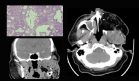

Los resultados de la biopsia cutánea, obtenidos diez días después del ingreso, revelaron hallazgos histopatológicos característicos de dermatitis carencial, incluyendo hiperqueratosis paraqueratósica, pérdida de la capa granulosa e hiperplasia epidérmica psoriasiforme.

Aunque estos hallazgos podrían corresponder a varias deficiencias nutricionales, el contexto clínico de resección intestinal extensa y el patrón de distribución de las lesiones orientaron hacia un diagnóstico de acrodermatitis enteropática adquirida secundaria a deficiencia de zinc.